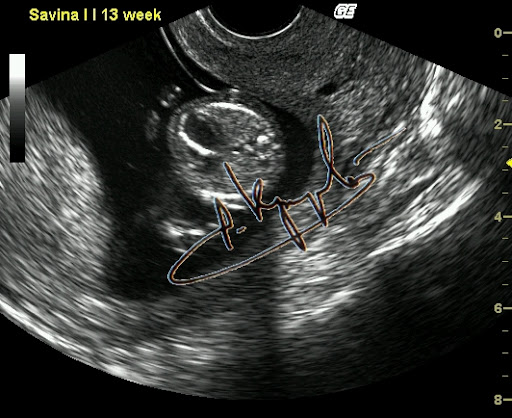

Фиброэластоз эндокарда. Диагностика на ранних сроках возможна.

Вот как быть? Вроде обещал нескольким человечкам рассказать про внутриутробный фак, но совершенно не уверен что получится что-то путнее. Хотя чем черт не шутит. Попробую. Было это буквально на днях, в четверг. Но лучше издалека начать. С именем Настя у меня по жизни непременно связан какой-то налёт чудесатости. Ну есть что-то такое... Что-то буквально на кончике не пойми чего. Как модно говорить "флёр @панутости". То, что даже издалека отличает любую Настю от носительниц других имен. Или, перефразируя вышесказанное, - нормальных Насть я в своей жизни пока не встречал. Это в качестве предисловия, хотя некоторые и осуждают любые эпиграфы. А кто сказал эпиграф? Я сказал - предисловие. Чуете разницу? Нет? Дело ваше. Полумрак кабинета. Беременность 24 недели. И Ваш покорный слуга, мучающий подслеповатые (уже весьма-весьма, увы) глаза перед экраном, согнувшись над животиком. УЗИ делаю. Сердце плода исследую (эхокардиография называется). Когда-то давно я эту методику отработал до совершенства. Ну то да сё, кровоток через клапаны, время изгнания, время релаксации и прочая хитромудрая мутотень. Тут Настя и говорит: - Ну что, показывает? Кто там у нас? (Настя - это беременная) - Какой пол? А разве не говорил на прошлом УЗИ? - Нет, не было видно. Ну это часто бывает. Вот втемяшится что-то ребятенку в животике и так упрется рогом в плаценту, то можно и до самых родов не узнать. Вот всеми возможными способами будет прятаться. То руками закрывать, то пуповину наматывать, то ноги сжимать. Ну бывает, поэтому особо не придал значения. Сердце закончил обследовать, - все нормально. И слава Богу. - Хорошо, говорю, - сейчас посмотрим кто-там прячется. Начал пытаться разглядывать. И так и сяк, короче и руку себе вывернул и глаза сломал. Потом на пару секунд плод ноги разжал и рукой, которой свою письку прикрывал, показал мне... натуральный фак. Секунды три подержал средний палец мне перед глазами и опять руки в промежность и ноги сжал. Я не выдержал и расхохотался. Мамашке говорю: - никогда мне еще за 25 лет с экрана плоды фак не показывали. Тут уже мамашка в хохот. Я весь в непонятках. А она мне: - Доктор, так в прошлый раз Вы тоже рассмотреть не могли, я три раза на кушетку ложилась и вставала. Но в тот раз ребенок вам... козу показывал. И правда. Вспомнил таки эту Настю. Кинулся искать в базе данных. И действительно - так и записано: Бурум-бурум Анастасия Паповна, Бер 18-19 нед, КЗ, ХЗ(показывала козу). И вот если бы мне кто рассказал, я бы не поверил. И главное - это оказалась девочка!!! Представляете, что за хулиганка растет? Кстати, у этой истории еще и продолжение есть. Но не сегодня.